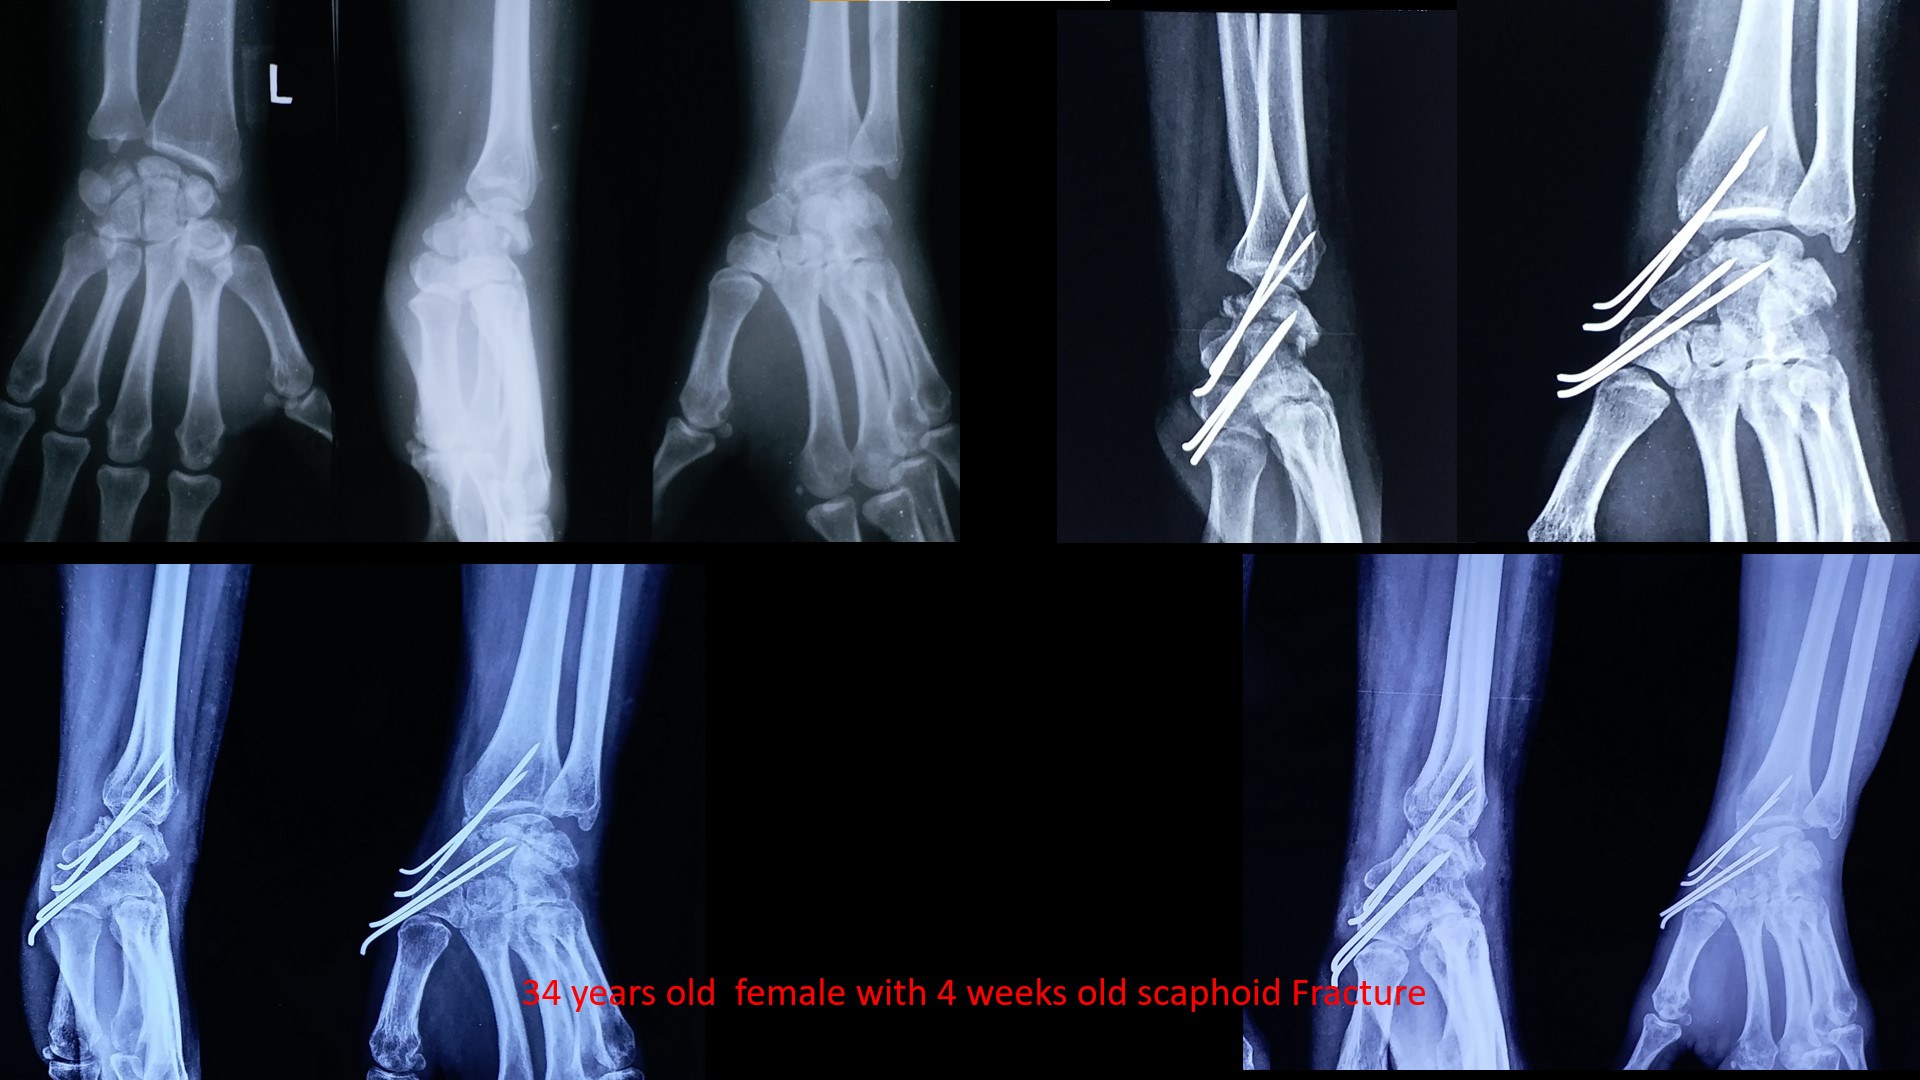

Fracture Scaphoid